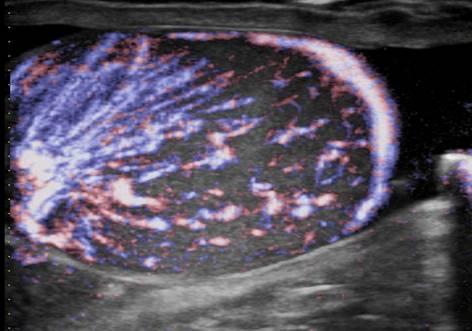

Viêm tinh hoàn - mào tinh

Viêm tinh hoàn – mào tinh

» Thông tin: Nam giới – 34 tuổi.

» Lâm sàng: Sưng đau vùng bìu.

# Tăng kích thước và tín hiệu mạch trên doppler tinh hoàn và mào tinh hoàn.